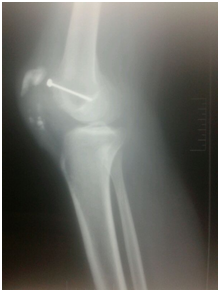

The tendon was sutured on itself by ethbound sutures, the side retinaculae was approximated and augmentation sutures was taken parallel to the tendon graft. The reconstruction was secured by stainless steel wire Figure 4 all circled around the patella and tibial tunnel. Release was done all sides of the knee to make knee flexion till 90 degrees. Closure in layers over suction drain and will padded pop back knee slab was done.

• Figure 4a & b Post operative plain X-ray.